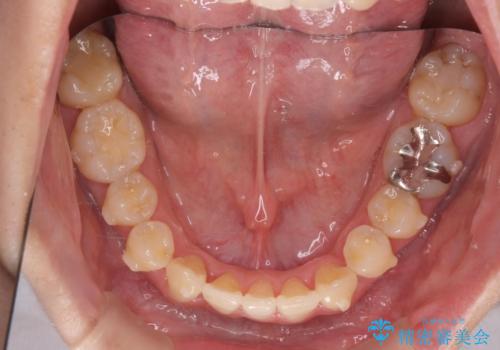

ねじれ・がたつきのある前歯を改善

- インビザライン +部分ワイヤー矯正

4本の小臼歯抜歯を避け、下顎前歯の1本抜歯の極力少ない抜歯本数で審美的な歯並びを得る治療計画としました。

すれ違いを治すのが得意な前歯部の部分ワイヤーを用いることで、治療期間を短縮することができました。

見た目の改善だけでなく、噛みやすくなったことにも満足いただくことができました。